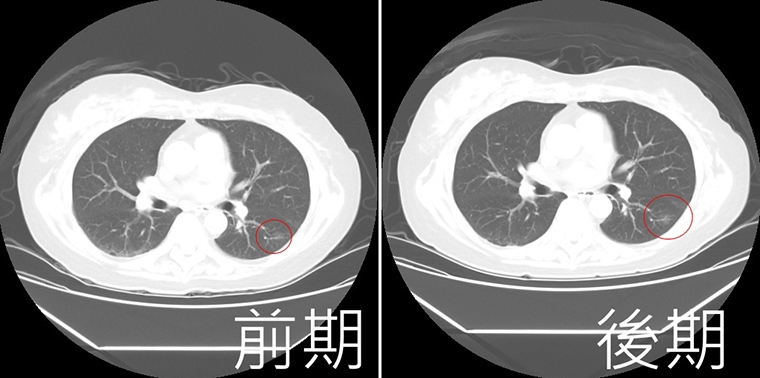

【NOW健康 陳郁茹/台中報導】71歲張阿嬤2年前安排「低劑量電腦斷層掃描」檢查,發現1顆0.8公分肺結節,當時醫師建議要定期追蹤,但她自認「沒有不舒服」,拖到今年才回診,結果肺結節長大1倍!阿嬤聽從醫囑接受微創手術,術中將結節送冷凍切片病理檢查,證實為早期肺腺癌,所幸癌細胞未擴散,術後3天即康復出院。

亞洲大學附屬醫院胸腔外科主治醫師劉柏毅指出,阿嬤的肺結節在2年前僅0.8公分,2年後卻已增大至1.5公分,考量到結節位置適合手術處理,因此進行微創肺段切除術,並在術中接受病理檢驗,冷凍切片結果確認為第1期肺腺癌,由於發現時間早,癌細胞尚未擴散,患者在術後第3天順利出院,後續檢查也顯示病情穩定。